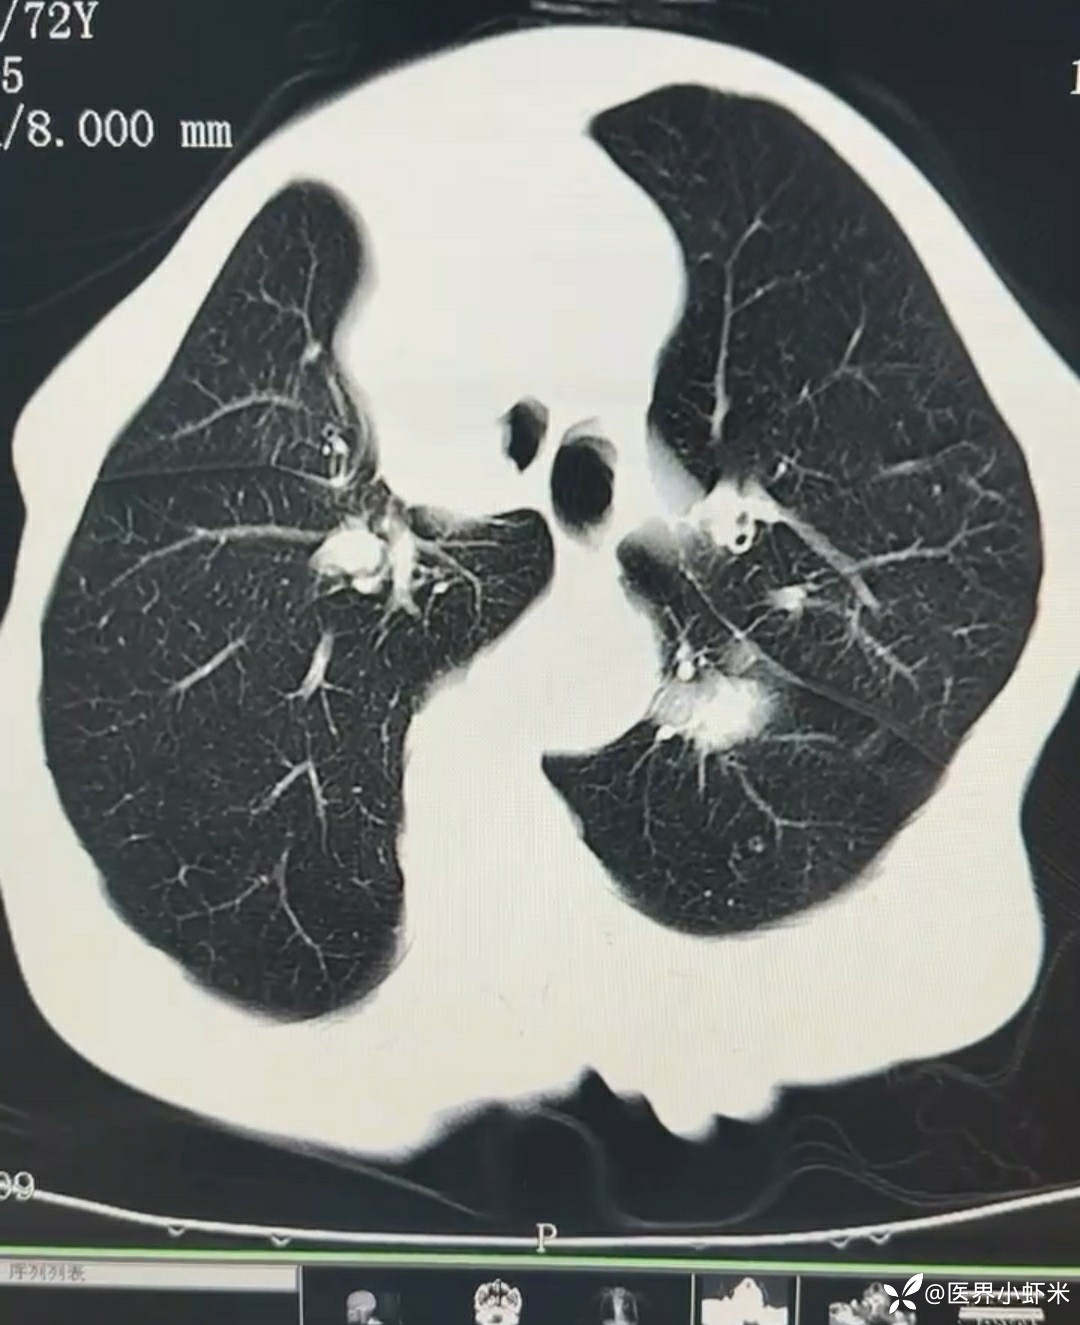

目前考虑:1.中央型肺癌伴2.肝继发恶性肿瘤?2.左丘脑继发恶性肿瘤?3.左丘脑出血?4.肾功能不全5.肝功能异常6右肾萎缩7.肺部感染8.慢性阻塞性肺病7.高血压3级(极高危)。